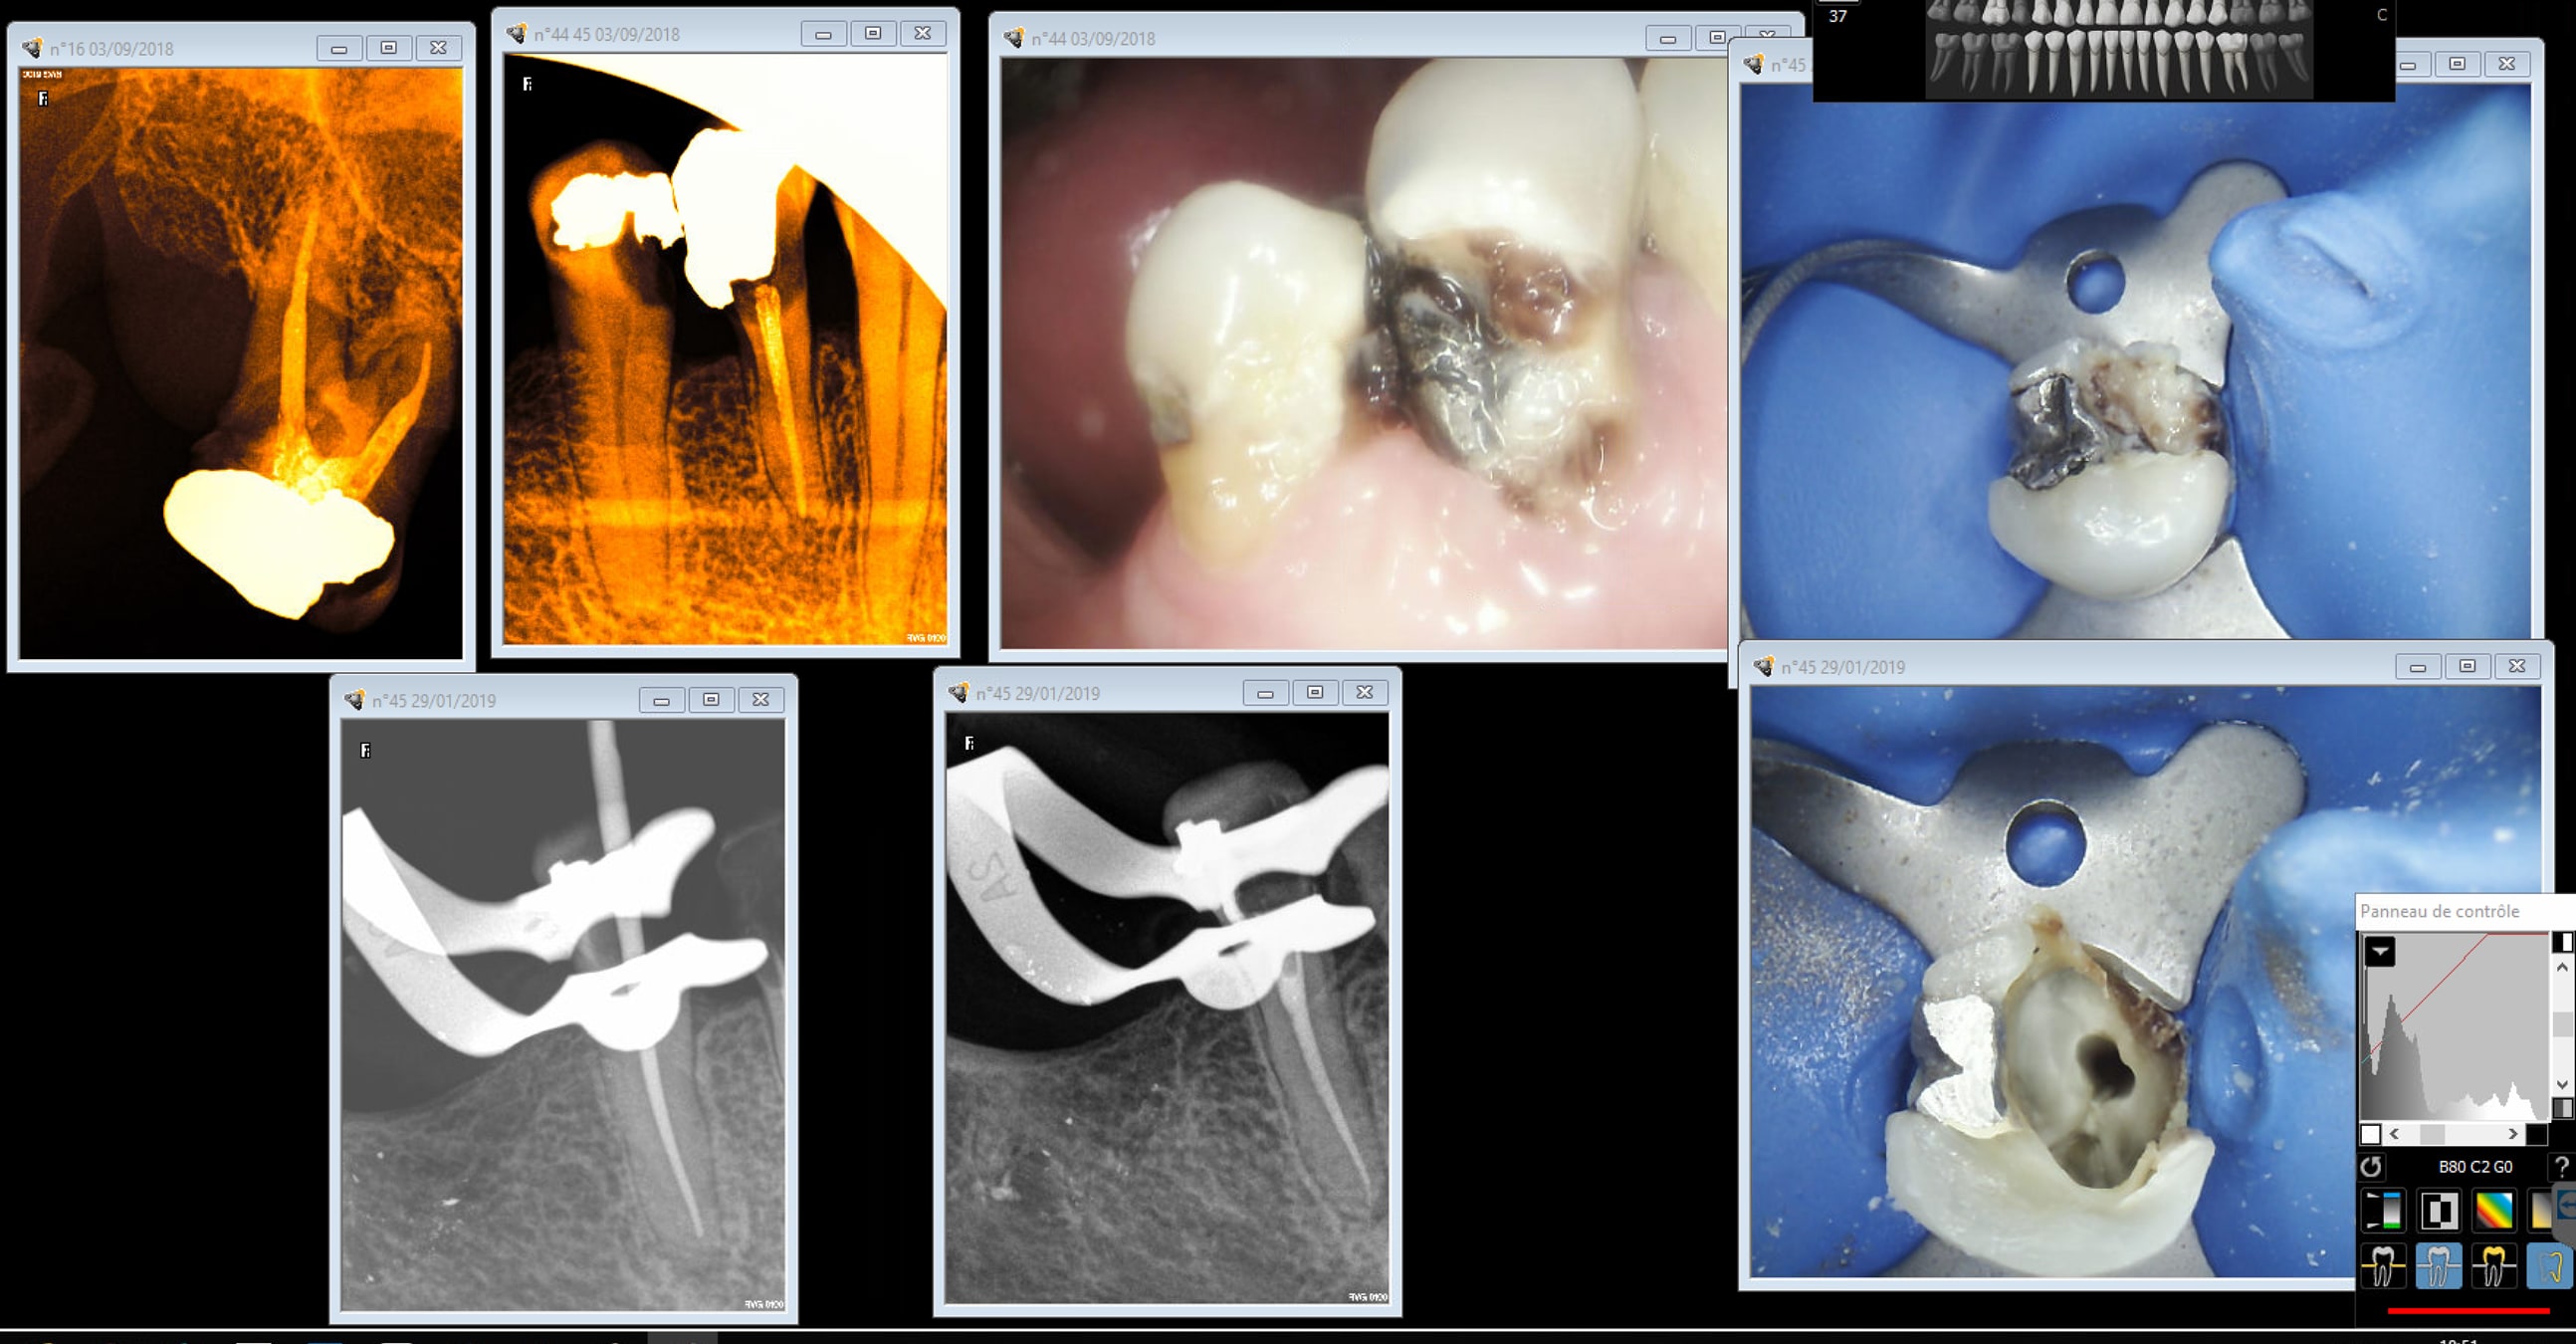

Pré prep ic cer 44 45 stellite one shot. Endo 45 réalisée . reste plus qu'à tailler. j'ai un doute pour 44 on va voir)

Capture d écran 2019 01 29 18.50 - Eugenol

Capture d écran 2019 01 29 18.51 - Eugenol

Capture d écran 2019 01 29 18.52 - Eugenol